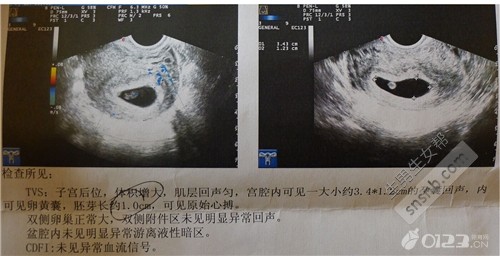

胎囊只在怀孕早期见到。月经28~30天规则来潮的妇女,停经35天,B超就可以在宫腔内看到胎囊。在怀孕6周时胎囊直径约2厘米,孕10周时约5厘米。胎囊位置在子宫的宫底、前壁、后壁、上部、中部都属正常;形态圆形、椭圆形、清晰为正常;如胎囊为不规则形、模糊,且位置在下部,孕妇同时有腹痛或阴道流血时,可能要流产。

5周:胎儿长到0.4厘米,进入了胚胎期,羊膜腔扩大,原始心血管出现,可有搏动。B超可看见小胎囊,胎囊约占宫腔不到1/4,或可见胎芽。

6周:胎儿长到0.85厘米,胎儿头部、脑泡、额面器官、呼吸、消化、神经等器官分化,B超胎囊清晰可见,并见胎芽及胎心跳。

7周:胎儿长到1.33厘米,胚胎已具有人雏形,体节已全部分化,四肢分出,各系统进一步发育。B超清楚看到胎芽及胎心跳,胎囊约占宫腔的l/3。

8周:胎儿长到1.66厘米,胎形已定,可分出胎头、体及四肢,胎头大于躯干。B超可见胎囊约占官腔1/2,胎儿形态及胎动清楚可见,并可看见卵黄囊。

9周:胎儿长到2.15厘米,胎儿头大于胎体,各部表现更清晰,头颅开始钙化、胎盘开始发育。B超可见胎囊几乎占满宫腔,胎儿轮廓更清晰,胎盘开始出现。

10周:胎儿长到2.83厘米,胎儿各器官均已形成,胎盘雏形形成。B超可见胎囊开始消失,月芽形胎盘可见,胎儿活跃在羊水中 。

11周:胎儿长到3.62厘米,胎儿各器官进一步发育,胎盘发育。B超可见胎囊完全消失,胎盘清晰可见。

12周:胎儿长到4.58厘米,外生殖器初步发育,如有畸形可以表现,头颅钙化更趋完善。颅骨光环清楚,可测双顶径,明显的畸形可以诊断,此后各脏器趋向完善。